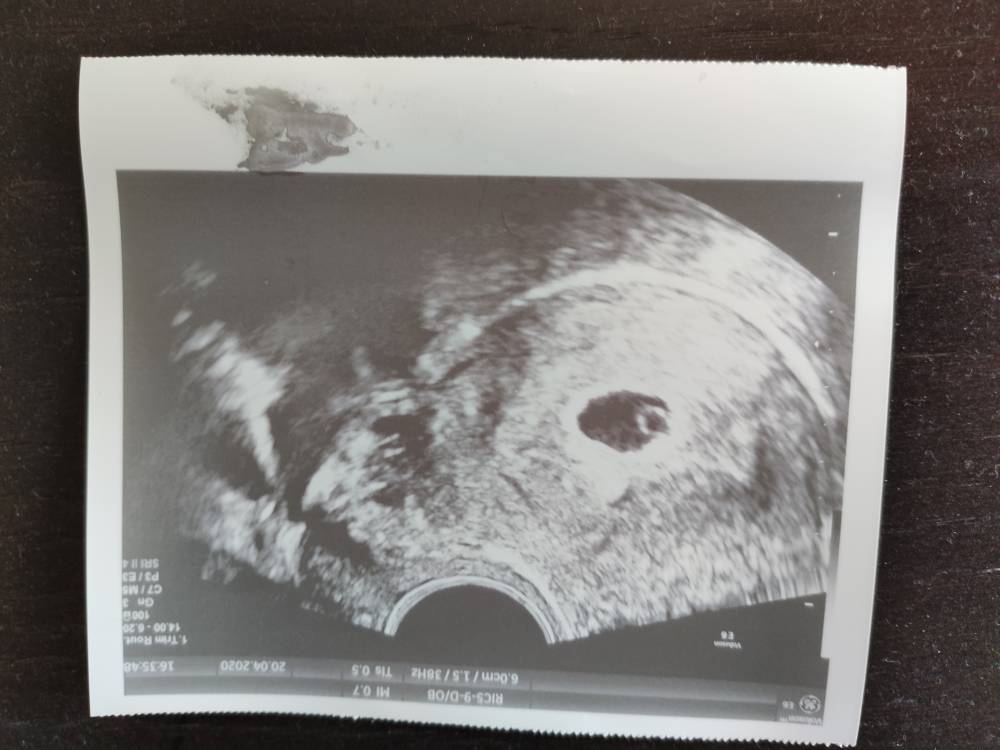

GratulacjeMoże coś napiszę o sobie mam 27 lat pierwsza ciąża jak na razie 6t+1d. Termin z OM mam na 16.12. następna wizytę mam na 4 maja.Zobacz załącznik 1110381Zobacz załącznik 1110382

27 lat, pierwsza ciąża i z dzisiejszego usg 6+1